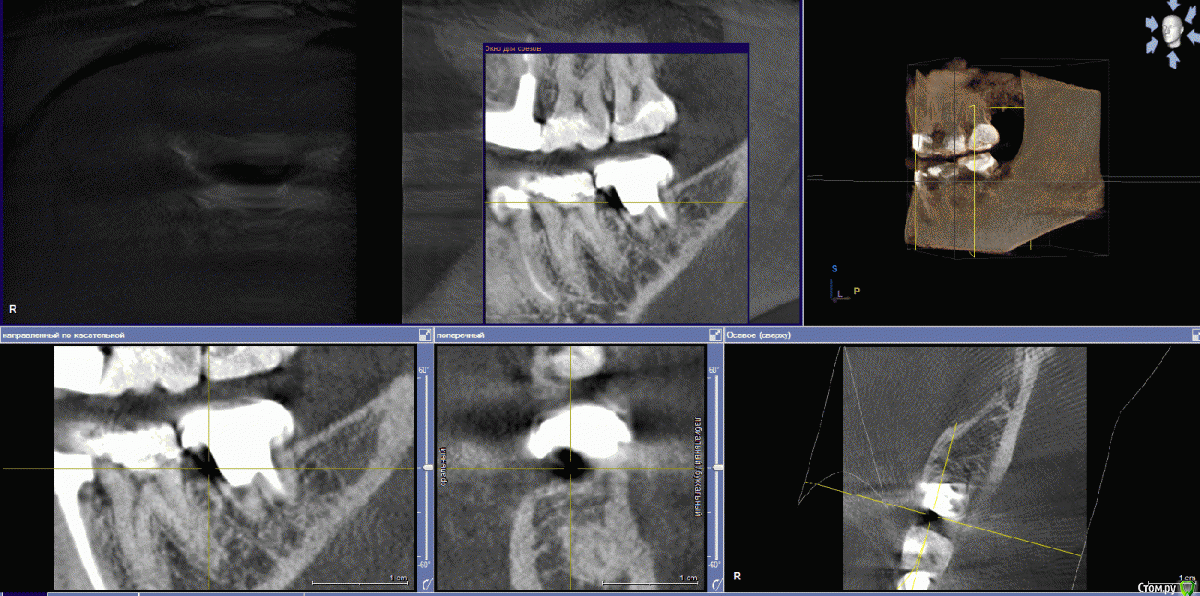

Jaz Опубликовано 23 сентября, 2017 Поделиться Опубликовано 23 сентября, 2017 (изменено) Здравствуйте!Итак, имеется в наличии зуб 47 (или 37? в общем, нижняя левая семерка). Года три как депульпирован, установлена вкладка и металлокерамика (материалы не знаю). По КТ нашли кариес под коронкой и кариес корня, т.е. 100% удаление.Жевательных зубов у меня и так прискорбно мало. Хочу ставить имплант. Но начиталась таких ужасов про имплантацию, что хотела бы собрать мнения знающих людей, прежде чем начинать сию операцию. совершенно запуталась в обилии информации. 1) одномоментная или классическая? Зуб еще на месте, и, как я поняла, лучше ставить имплант сразу после того, как зуб выдерут? Никаких заболеваний у меня вроде нет (но может нужно какие анализы сдать и провериться? на диабет меня не проверяли просто)2) нужна ли в моем случае подсадка кости или какие-то иные манипуляции, требующие затрат (планирую брать кредит, момент важный)3) у меня глубины и ширины кости вообще для имплантации хватает? или мне морально готовиться к вставной челюсти в 30 лет?3) прочитала здесь на форуме, что на нижние семерки сразу нагрузку не дают. Но разве это не приведет к деградации кости?4) какой производитель все же лучше? Насчет коронки, как я понимаю, лучше цирконий? Я работаю с химикатами (формалин, ксилолы, фиксаторы и вся прочая патологоанотомическая каша) - есть в этом случае какие-то нюансы в выборе материала для штифта и коронки? Прилагаю снимки КТ. Толком не поняла, как их в программе делать. Если что - переделаю. Изменено 23 сентября, 2017 пользователем Jaz Ссылка на комментарий

колесников Опубликовано 23 сентября, 2017 Поделиться Опубликовано 23 сентября, 2017 (изменено) Здравствуйте! В вашем случае предпочтение к одномоментной имплантации. (Костной ткани достаточно для первичной стабильности импланта,но есть тенденция к образованию узкого гребня после удаления). Из дополнительных расходов будет:удаление зуба,0.5 г кости,возможно пересадка лоскута десны,установка формирователя десны.Систему лучше выбирать совместно с вашим доктором. Изменено 23 сентября, 2017 пользователем колесников Ссылка на комментарий